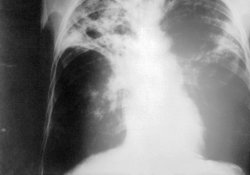

живу по временной регистрации.

у меня обнаружили очаговый туберкулез верхней доли правого легкого.положили в диспансер на месяц ,выписали на амбулаторное лечения лечусь 5 месяцев.заключения первого кт:картина очагового туберкулеза легких,гидроторакс справа. I A группа учета лечения по III режиму,изониазид 0,6 рифампицин 0,6 этамбутол 1,2 последний после трех месяцев лечения отменили оставили два препарата.лечусь 5 месяцев

через 2 месяца заключение КТ: признаки конгломератных туберкулом 1-2 сегментов правого легкого.